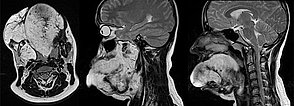

Sagittal and axial T2-weighted MRI of the face shows the extensive venous malformation located in the whole tongue and right cheek muscles.